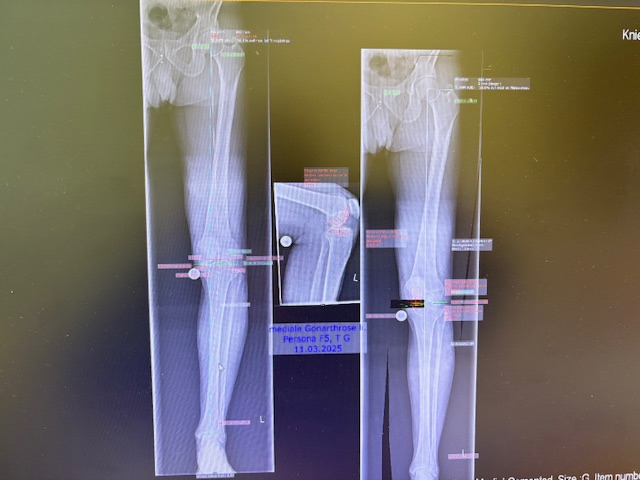

Ο ακτινολογικός έλεγχος (ακτινογραφίες/μαγνητική τομογραφία) ανέδειξε προχωρημένη οστεοαρθρίτιδα του έσω κονδύλου, με πλήρη διατήρηση του έξω διαμερίσματος και της επιγονατιδομηριαίας άρθρωσης. Με βάση αυτά τα ευρήματα, ο ασθενής ήταν ιδανικός υποψήφιος για μερική (μονοκονδυλική) αρθροπλαστική γόνατος.

Πραγματοποιήθηκε απεικόνιση και ψηφιακός σχεδιασμός της επέμβασης, ώστε να προσδιοριστεί με ακρίβεια το μέγεθος και η θέση των προθέσεων. Ο στόχος ήταν να αποκατασταθεί η φυσιολογική μηχανική του γόνατος, διατηρώντας ανέπαφα τα υγιή τμήματα της άρθρωσης, τους συνδέσμους και τους γύρω μυς.

Στον ασθενή τα εμφυτεύματα που χρησιμοποιήθηκαν είναι της εταιρείας Zimmer-Biomet Persona Μηριαίο μέγεθος 6, κνημιαίο μέγεθος Η και ενθέμα (inlay) Η li. 8mm.